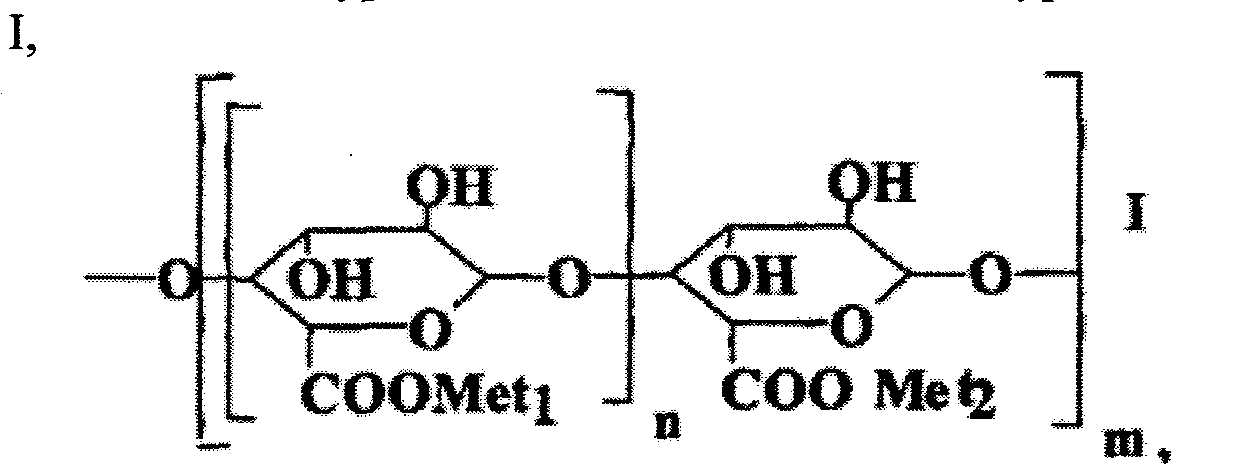

| 16. | 1. | 2574397 (21), (22) Заявка: 2015104887/04, 13.02.2015 (24) Дата начала отсчета срока действия патента: 13.02.2015 (45) Опубликовано: 10.02.2016 (51) МПК C07D285/18, A61K31/54, A61P31/14 (72) Авторы: Иващенко Александр Васильевич, Иващенко Андрей Александрович, Бычко Вадим Васильевич, Хват Александр Викторович, Савчук Николай Филиппович, Роговой Борис (73) Патентообладатель: Иващенко Александр Васильевич, АЛЛА ХЕМ, ЛЛС Адрес для переписки: 141401, Московская обл., г. Химки, ул. Рабочая, 2а, корп. 1, ЦВТ "ХимРар", Шмаковой Е.А. (54) Бензо[1.2.4] тиадиазиновые ингибиторы репликации вируса гепатита В и фармацевтическая композиция для лечения гепатита В |

Изобретение относится к новым ингибиторам репликации вируса гепатита В, представляющим собой 1,1-диоксо-1,4-дигидро-2Н-бензо[1,2,4]тиадиазин-3-оны общей формулы 1, их фармацевтически приемлемые соли и/или гидраты. В общей формуле 1

где

где  и

и  представляют собой фенил, необязательно замещенный одним, двумя или тремя одинаковыми или различными заместителями, выбранными из

представляют собой фенил, необязательно замещенный одним, двумя или тремя одинаковыми или различными заместителями, выбранными из  , метоксила, галогена, карбоксила и карбонитрила. Изобретение также относится к фармацевтической композиции в форме таблеток, капсул или инъекций, помещенных в фармацевтически приемлемую упаковку, для лечения гепатита В и к способу профилактики или лечения гепатита В.

, метоксила, галогена, карбоксила и карбонитрила. Изобретение также относится к фармацевтической композиции в форме таблеток, капсул или инъекций, помещенных в фармацевтически приемлемую упаковку, для лечения гепатита В и к способу профилактики или лечения гепатита В.